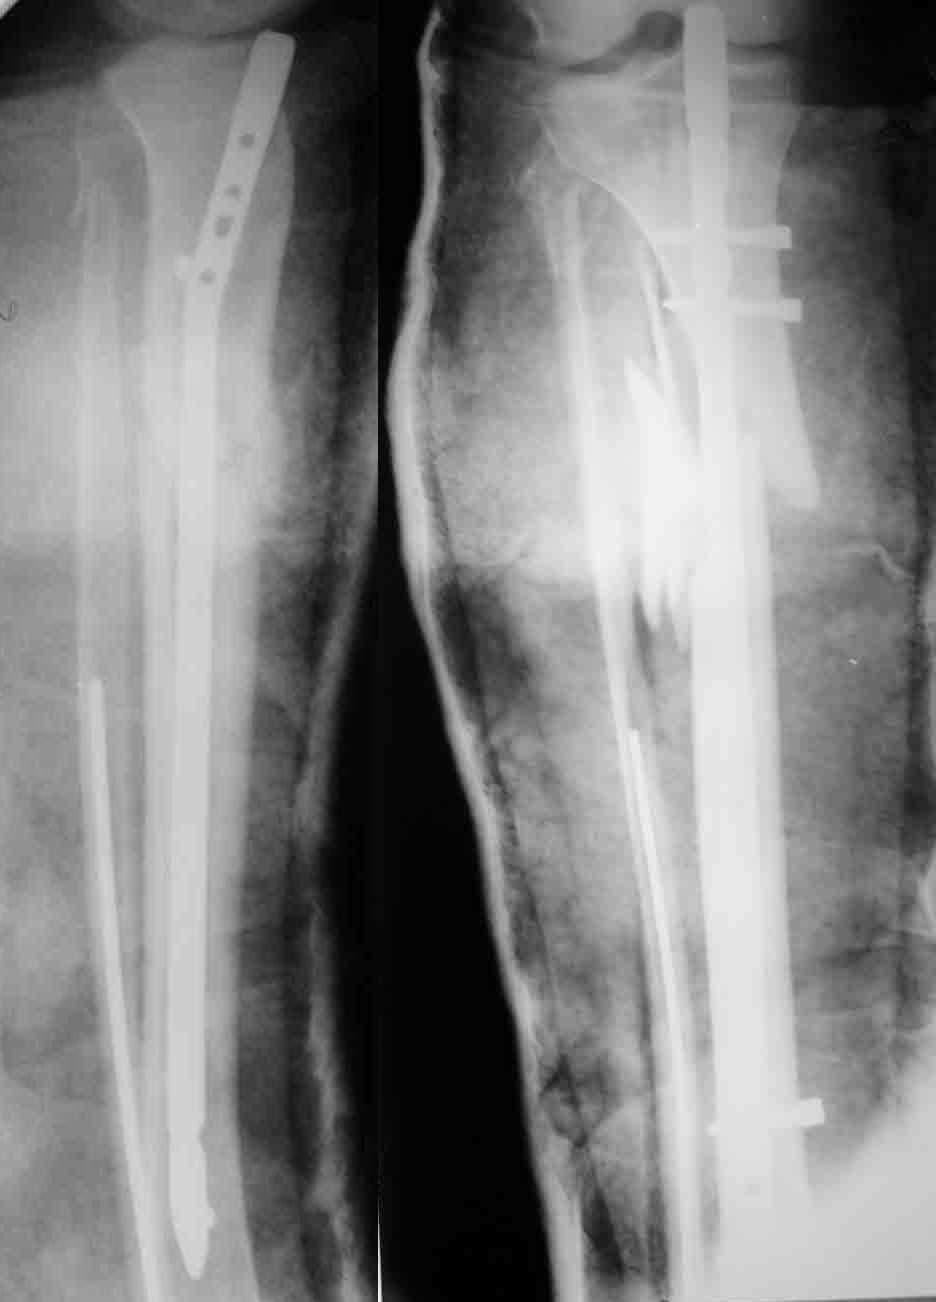

Enes Kanlic 18 Декабрь 2003, 10:08

1

2

3

4

5

6

I agree with Dr. Wilson,

In general:

1. Nailing proximal tibias: Starting point has to be high (still not to

penetrate knee capsule) and a little bit lateral from midpoint. Blocking

screws are very helpful and sometimes necessary, see attached Slides 1 and

2).

2. Plate could be used, just needs to be done right (minimally invasive,

preservation of soft tissues, slides 4 and 5)

3. If it is impossible to get reduction trying to pass the nail distally,

plate could be added (as on slides 5 and 6).

In this particular patient, if soft tissues are good, I would:

A) Exchange (closed method) the nail (shorter one, starting point a little

bit more lateral) and blocking screws probably would be needed, and if that

does not work

B) I would open the fracture, would help my reduction with forceps or plate

and still nail it.

If somebody is not comfortable with this techniques, probably the safest way

(not and most comfortable and convenient for the patient) is to go for ring

external fixator (Ilizarov type).